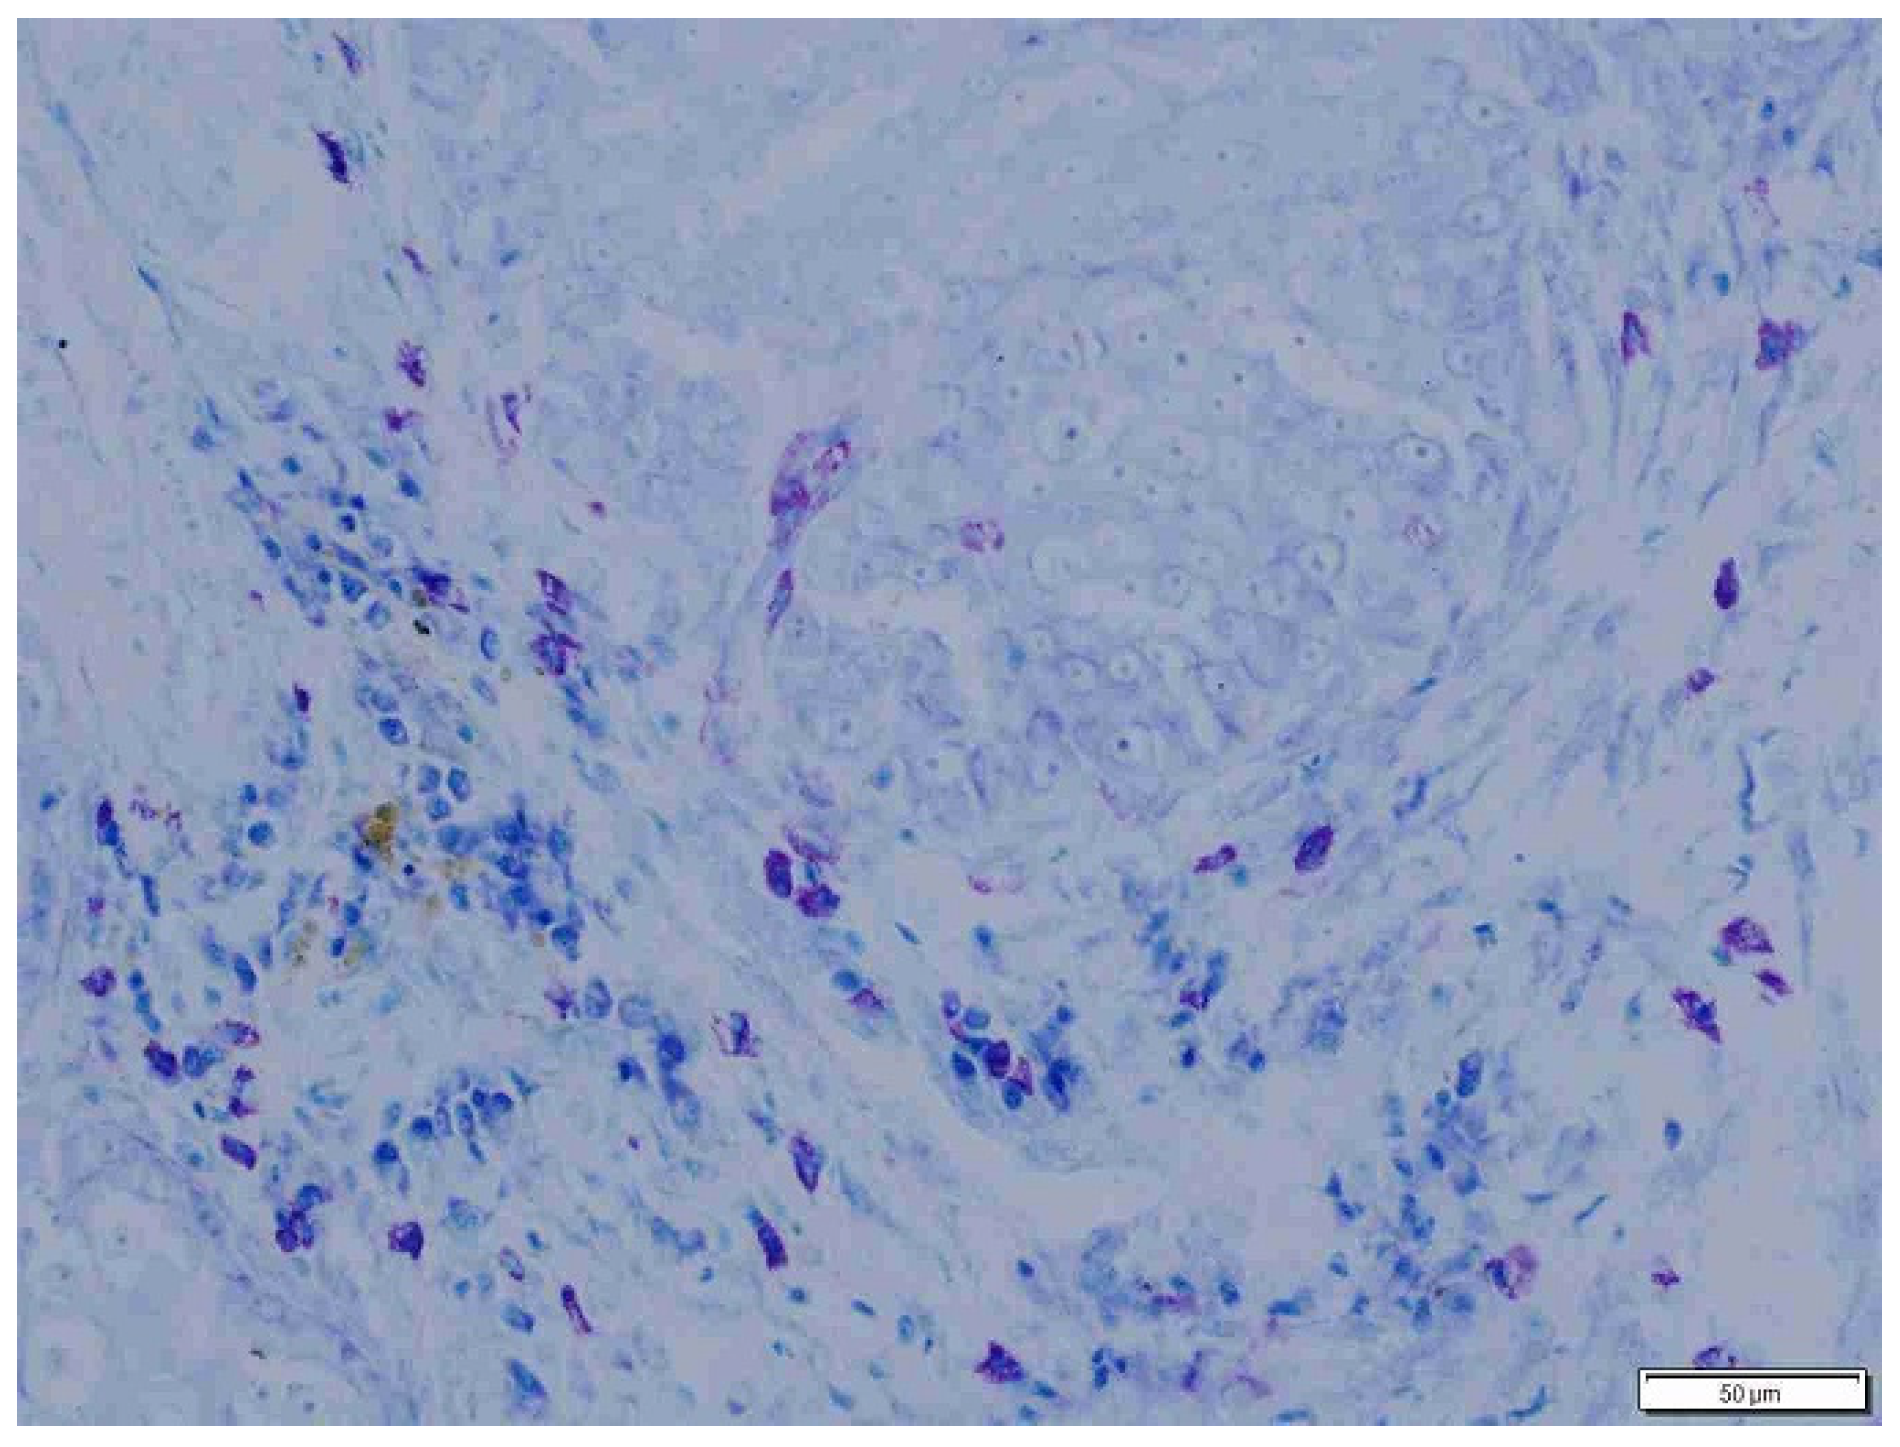

2.4. Histopathology

3. Results

| Total PTMC | 136.53 ± 59.34 a3 | 202.96 ± 110.21 b3 |

| Total ITMC | 75.3 ± 18.06 a6 | 200.1 ± 106.27 b6 |

| Total MC | 211.83 ± 46.15 a7 | 403.01 ± 107.34 b7 |